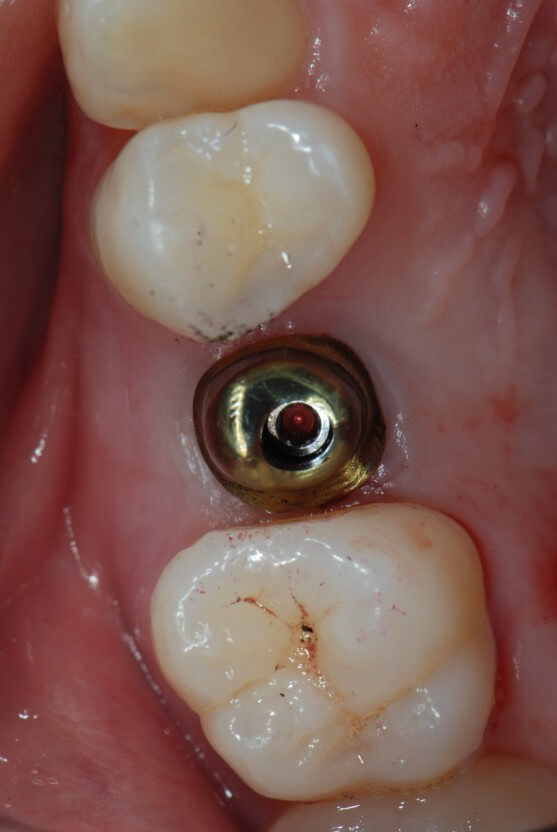

임플란트는 쉽게 말씀드리면 치아를 제거한 부위에 인공적으로 만든 치아를 즉, 임플란트를 식립 하는 시술입니다.